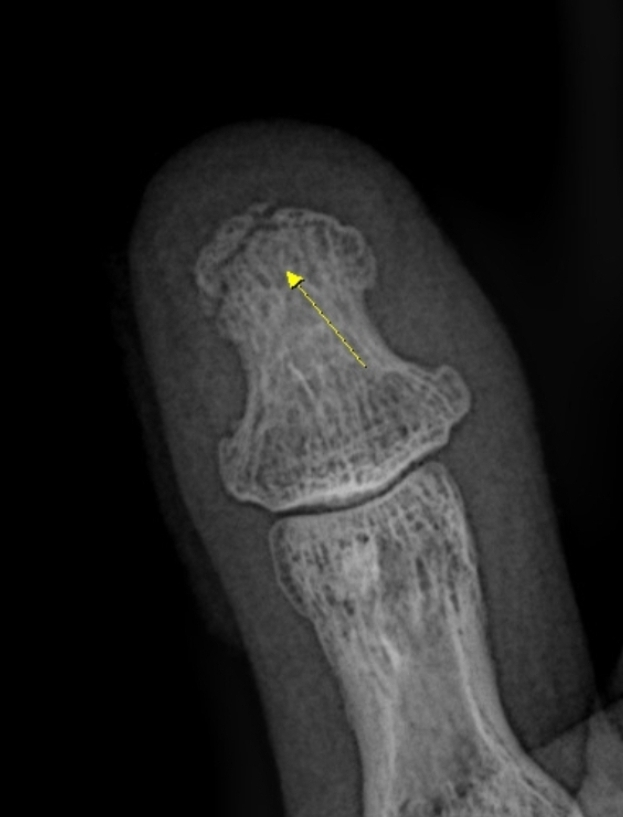

엄지손가락 끝쪽 3mm정도 골절인데 적절한 치료방법이 어떤방법이 있을까요?

사진처럼 근무중 바람에 움직이는 철문사이에 끼여 엄지손가락끝이 3mm정도 골절되어 진단을 받고 일쥘정도 통원치료를 받았는데요..골절부위가 작아서 수술은 안된다고 합니다..골절된 뼈도 붙지가 않는다고 하는데 다른 방법은 정말 없는 걸까요? 그냥 저 상태로 조심히 생활해야 하는걸까요?

동네 정형외과의원, 대학병원 정형외과 다 가봤는데 모두 비슷한 소견을 받았습니다..